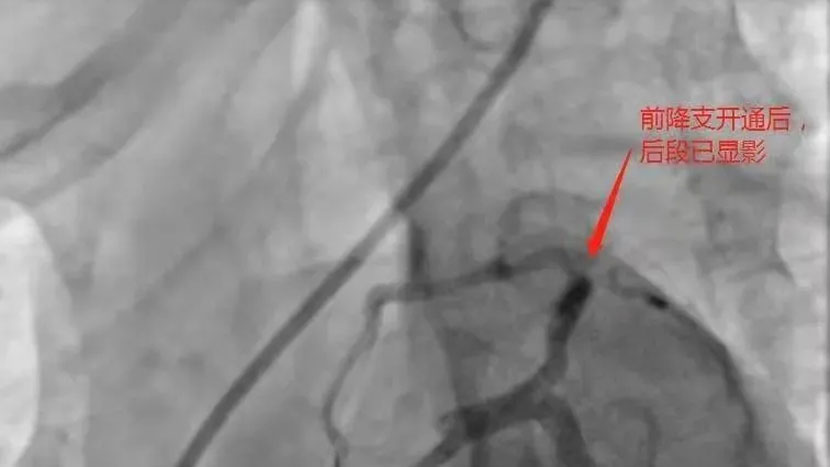

据了解,该患者为34岁男性患者,1年前在上级医院已做过支架植入术,近期反复熬夜及劳累,前段时间已经开始有胸痛症状,因为上过支架没有引起重视,12月31日早上10时许胸痛加重,14:20分进入我院急诊科,急诊科值班医师通过简单询问,14:27分完善首份心电图,考虑广泛前壁心肌梗塞可能,立即上传心电图于来凤县胸痛中心群,心内科值班医师立即建议阿司匹林肠溶片300mg.氯吡格雷600mg,瑞舒伐他汀钙20mg,此时该院常规冠状动脉造影术刚结束,导管室护士正在清理东西准备关闭导管室,心内科朱主任看见上述情况后立即通知导管室做好准备,亲自到急诊科评估患者情况,并电话立即联系副院长兼心内科主任张承中以及刚做完手术回家的恩施慧宜医疗集团张宏伟教授,张宏伟教授了解情况后建议立即开展急诊冠状动脉造影,绕行CCU,直接由急诊科送入导管室,14:50分进入导管室,造影可以看见前降支近端闭塞,原支架内大量血栓堵塞,15:30经球囊扩张后,患者血流有所恢复,因前降支原支架内大量血栓,术中又使用腔内溶栓术、预扩球囊刺破腔内给药、血栓抽吸术等,患者前降支闭塞血管血流恢复,仅用70分钟,为患者开通血管,挽救了患者年轻生命。